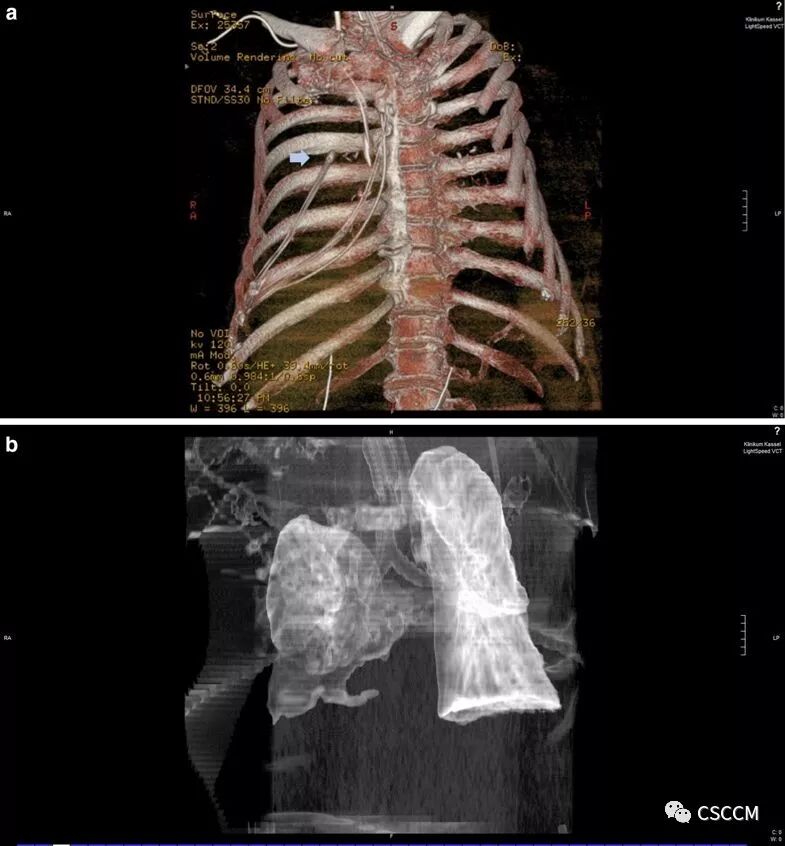

An 89-year-old woman was treated in our intensive care unit with Escherichia coli urosepsis. The patient developed multiple organ failure and became intubated and mechanically ventilated. On the third intensive care day, a new 16Fr. type “Levin” nasogastric tube was inserted for enteral feeding. As no anatomical abnormalities were described, we followed a blind insertion technique, encountering no resistance while advancing the tube towards the stomach, and final position was confirmed by auscultation of a gurgling noise over the epigastrium. Enteral nutrition was started, according to ICU feeding protocol. However, 48 h later, acute hemodynamic instability was observed and invasive mechanical ventilation became difficult. A bed-side ultrasonography showed a pleural effusion on the right side, and a puncture for pleural-catheter placement revealed nutrition in the pleural space. 3D-reconstructed images of a chest computed tomography (Fig. 1a, arrow) demonstrated the endpoint of the nasogastric tube into the right pleura, confirming the perforation of the right lower lobe bronchus and massive lung parenchyma damage (Fig. 1b), despite the patient having an endotracheal tube in situ and giving no signal of cuff insufficiency. We suggest that radiological control remains the standard procedure to confirm the correct position of a nasogastric tube, even by invasive ventilated patients.

一名89岁女性患者因大肠杆菌泌尿系感染导致sepsis在ICU接受治疗。患者出现多器官功能衰竭,接受气管插管和机械通气。入住ICU的第三天,置入16 F的Levin型鼻胃管进行肠内营养。由于未发现任何解剖学异常,我们采用盲法置入,将鼻胃管送入胃内时未遇到任何阻力,置管结束后在上腹部听诊到气过水声确认导管位置。根据ICU喂养方案开始肠内营养。然而,48小时后,患者出现血流动力学不稳定,有创机械通气难以维持。床旁超声检查显示右侧胸腔积液,置入胸腔引流管发现胸腔积液为营养液。胸部CT检查三维重建(图1a,箭头)显示鼻胃管末端位于右侧胸腔内,确诊右下叶支气管穿孔及大面积肺实质损害(图1b)(尽管患者有气管插管且没有套囊漏气的表现)。我们建议,即使对于接受有创机械通气的患者,影像学检查仍然是确认鼻胃管位置正确与否的标准措施。